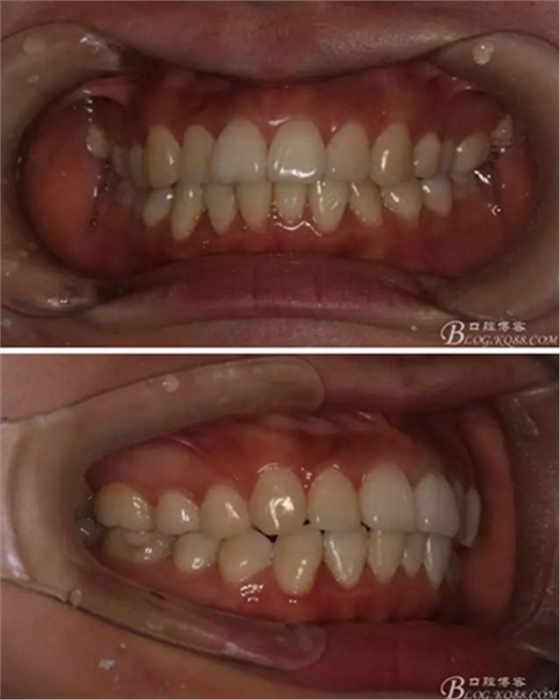

患者,女,主訴:牙齒不齊。

如圖,該病例為簡單排齊病例,但77鎖合是矯治中的關(guān)鍵所在,你會怎么處理?